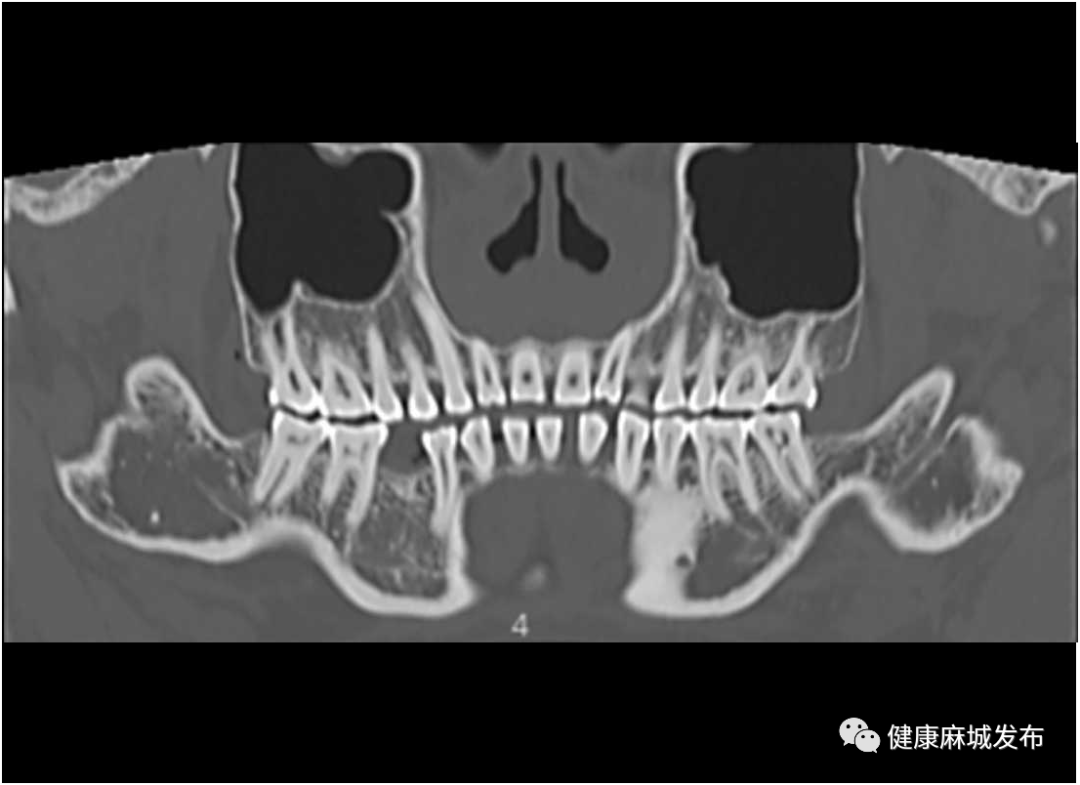

齿科应用:全景展示口腔内牙齿的分布,形态,显示下颌神经管的走形和位置。为口腔科,颌面外科,整形科带来更多便利。